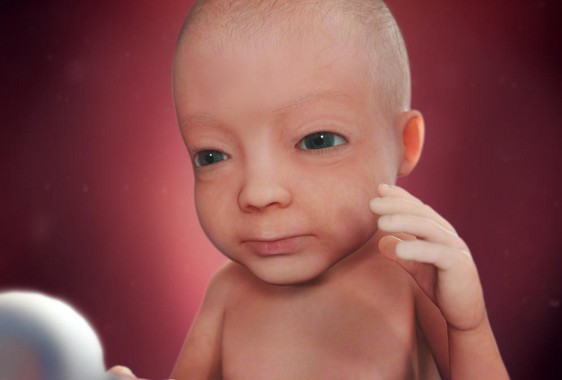

الأسبوع الثامن والثلاثون

يتكمل نمو الطفل خلال هذا الأسبوع ويصبح على استعداد لأن يتم ولادته ويصبح وزن رأسه حوالي 400 جم أما عن وزن الجسم بشكل عام فيبلغ 2900جم .